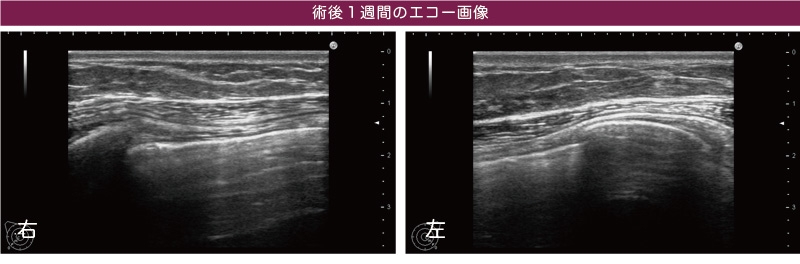

もうひとつ、THE CLINICでは術後のエコー検査も全例で実施します。何らかの後遺症が残るのを防ぐためです。シリコンが被膜内に流れ出ていた場合、抜去・洗浄した術後にリンパ液がたまる場合がありますが、今回は1週間後のエコーでもそのような問題は見つかりませんでした。

クリニック選びの際は「術前・術後のエコー検査」をしっかり実施しているかどうかをポイントにしましょう。